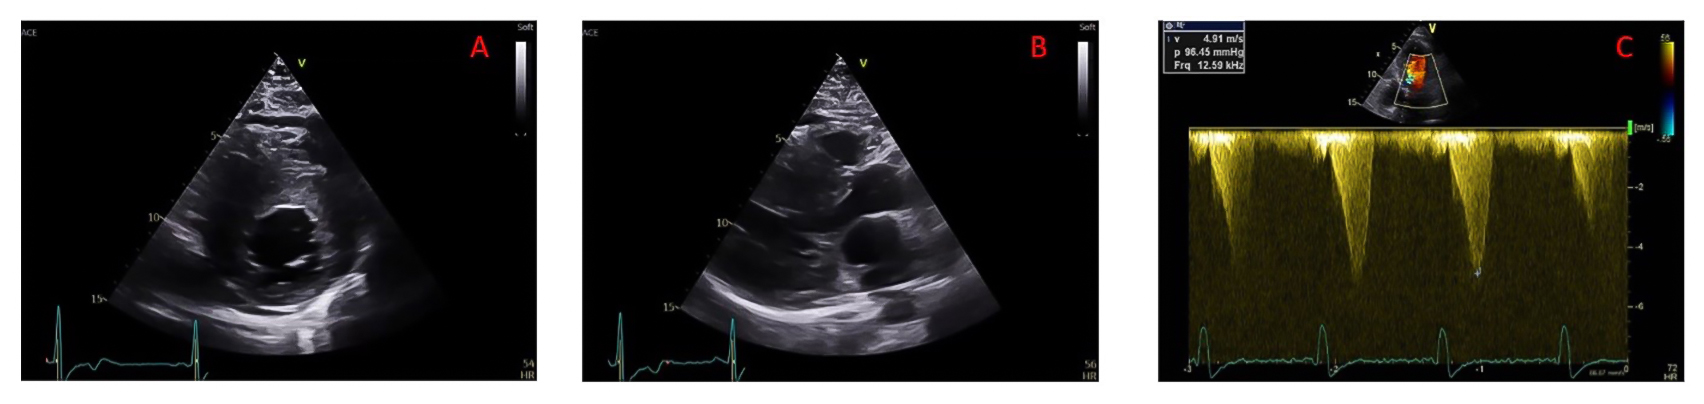

Figure 1. Echocardiographic risk markers used in the 2014 ESC SCD HCM risk score.

A) Parasternal short axis view in end-diastole to be used for measuring maximal LV wall thickness; (B) parasternal long axis view in end-systole to be used for measuring antero-posterior left atrial diameter; (C) Continuous wave Doppler measure of LVOT maximal gradient of obstruction.

LV: left ventricular; LVOT: left ventricular outflow tract

The 2014 European Society of Cardiology model introduced a formalised five-year risk calculator for SCD risk estimation. This model integrates clinical (age, family history of SCD, unexplained syncope, and non-sustained ventricular tachycardia) as well as echocardiographic variables, including maximal left ventricular (LV) wall thickness, maximal LV outflow tract (LVOT) obstruction gradient (either spontaneous or Valsalva manoeuvre-induced), and antero-posterior left atrial diameter acquired on para-sternal long axis view, into a quantitative estimate of five year risk (Figure 1).